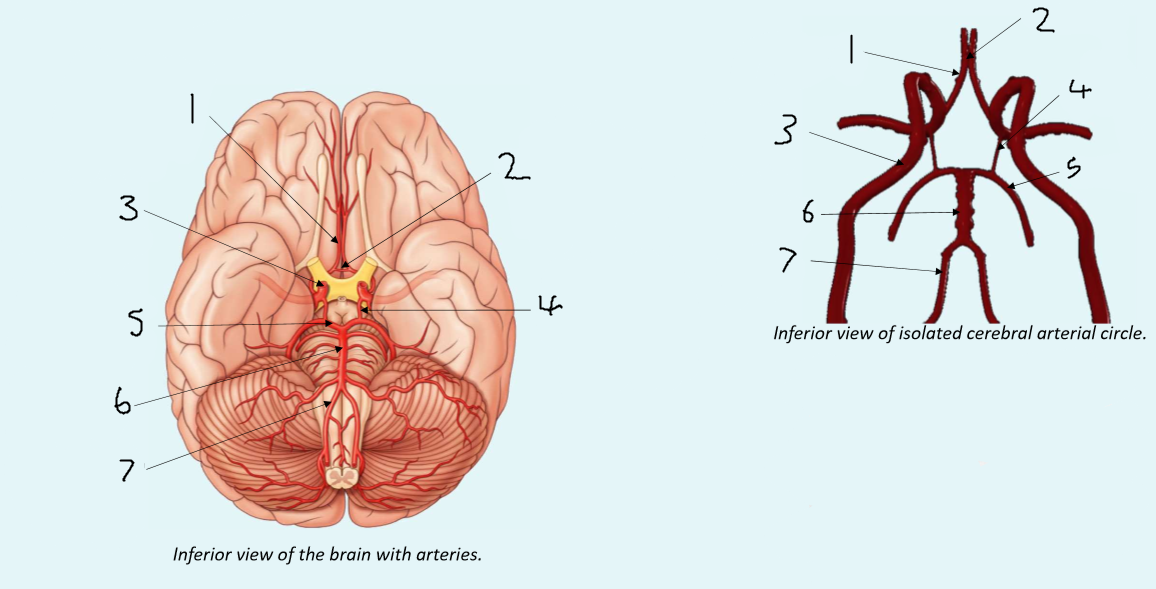

What is 1?

anterior cerebral artery

What is 2?

anterior communicating artery

What is 3?

internal carotid artery

What is 4?

posterior communicating artery

What is 5?

posterior cerebral artery

What is 6?

basilar artery

What is 7?

vertebral artery